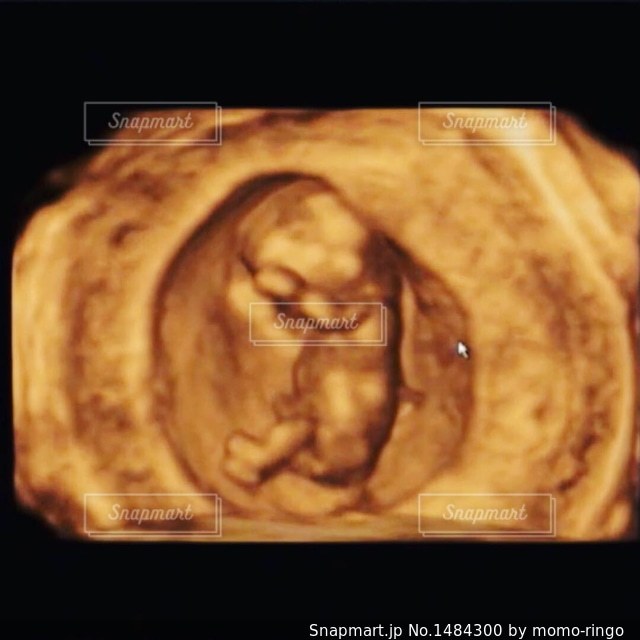

妊娠5ヶ月 妊娠16週,17週,18週,19週,妊娠中期 の超音波写真妊娠・出産・育児に関する総合情報サイト ベビカム。

妊娠5ヶ月 妊娠16週,17週,18週,19週,妊娠中期 の超音波写真妊娠・出産・育児に関する総合情報サイト ベビカム。

妊娠5ヶ月 妊娠16週,17週,18週,19週,妊娠中期 の超音波写真妊娠・出産・育児に関する総合情報サイト ベビカム。